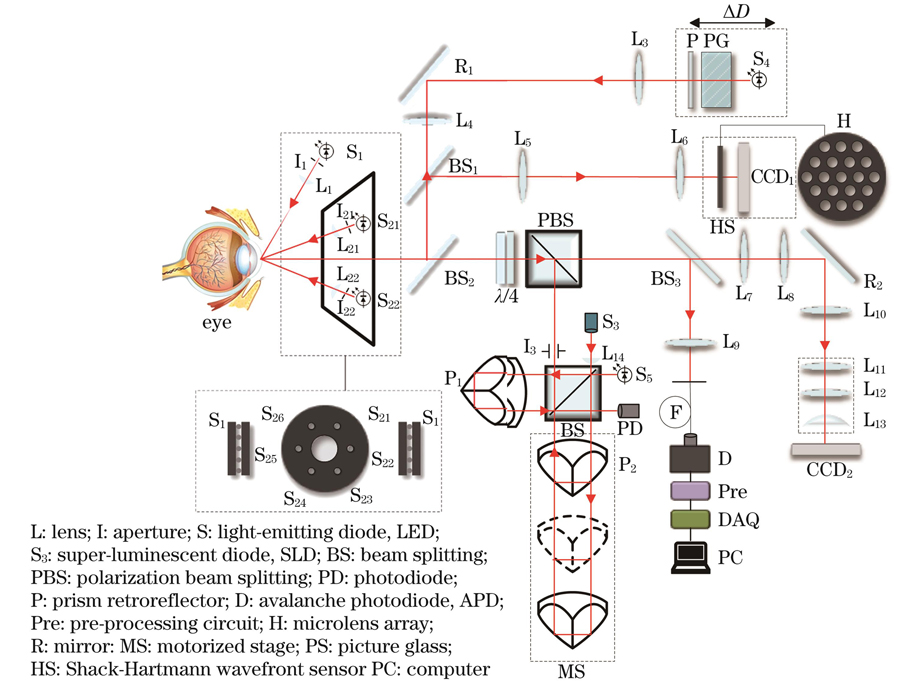

An integrated system for the measurement of the ocular refractive error and ocular biometry consists of a Twyman-Green low-coherence interference subsystem and a Shack-Hartmann wavefront sensing subsystem (Fig.1). A super-luminescent diode (SLD), beam splitter (BS), prism retroreflector, polarization beam splitting (PBS), and avalanche photodiode (APD) compose the Twyman-Green low-coherence interference subsystem. The SLD of the Twyman-Green low-coherence interference subsystem, lens relaxed optical path, and Shack-Hartmann wavefront sensor form the ocular refractive error-measuring optical subsystem. The axial length of the human eye was measured based on the Twyman-Green low-coherence interference system. Corneal reflex imaging was used to measure the corneal curvature. Measurement of anterior chamber depth is achieved in combination with slit lamp and corneal curvature measurement. The integrated design was applied in the optical system design and fused wavefront aberration analysis and interference optical paths; the strict collimation SLD could be a shared source to achieve wavefront aberration analysis and eye-axis measurement. Diopter measurements were calibrated using standard model eyes to ensure the accuracy of the measurement results. The biological parameters of the human eye (AL, K, and ACD) and diopter (spherical and cylindrical degrees) were measured five times for each subject using the experimental prototype and IOL Master 500, respectively. All statistical analysis were performed using SPSS 25.0 software. The repeatability of the experimental prototype measurements was evaluated using the within-subject standard deviation(Sw), test-retest repeatability (TRT), coefficient of variation (CoV), and intra-group correlation coefficient (ICC). The measurement results of the experimental prototype and IOL Master 500 were compared to analyze their accuracy and consistency.

在前期的研究中,本团队建立了眼的波像差分析系统和眼生物参数测量系统。前者主要通过夏克-哈特曼(Shack-Hartmann)波前传感器实现人眼主客观波像差(包括球差和像散特性)分析[20];后者基于泰曼-格林(Twyman-Green)低相干干涉系统测量人眼的眼轴长度[21-22],采用角膜反射成像技术实现角膜曲率的测量,利用裂隙灯与角膜曲率测量实现前房深度的测量。基于上述基础,融合波像差分析系统和干涉系统,经过严格准直激光,可以共用同一个光源实现波像差和眼轴测量。具体的光路设计如

图 1. 眼屈光度与生物参数测量一体化设计光路图

Fig. 1. Optical path diagram with integrated design of eye refraction and biological parameter measurement

2.2 眼轴长度测量光路设计

本团队设计的眼轴长度测量系统[21](New AL)是基于双光路外差干涉原理搭建的泰曼-格林干涉系统,该系统主要由近红外超辐射发光二极管S3(中心波长为790 nm,带宽为30 nm,偏振度为1000∶1)、准直镜L14、分光棱镜BS(分束比为50∶50)、角锥棱镜P1和P2、光电探测器D和数据采集卡(DAQ)组成。干涉信号经光电探测器转换为电信号后再由前置放大器Pre放大,之后被数据采集卡采集并被输入计算机,对数据进行分析即可得到眼轴长度。

2.3 角膜曲率测量光路设计

角膜曲率测量光路的设计原理是角膜反射成像。角膜曲率测量方法为:6个呈正六边形排布的LED光源(S21、S22等)经过1 mm孔径光阑(I21、I22等)后变为点光源,点光源经透镜(L21、L22等)准直后投射到角膜前表面,角膜反射的图像经L7、L8及L10~L13组成的物方远心光路后成像在CCD2上;利用重心算法求出角膜反射图像中位于正六边形长对角线上的两个点光源的距离,便可求得角膜曲率。

2.4 前房深度测量光路设计

LED光源S1发出的光经光阑I1、柱面镜L1形成裂隙光,裂隙光经眼睛的晶体和角膜反射后进入L7、L8及L10~L13组成的物方远心光路并成像在CCD2上,如

2.5 屈光度测量光路设计

在本设计中,采用准直的SLD(S3)激光作为参考波前的光源,其由眼轴测量光路进入人眼,经眼底反射后携带人眼的光学波前,经BS2、BS1以及透镜L5和L6组成的望远系统进入夏克-哈特曼波前传感器。其中,透镜L5、L6组成的望远系统将眼底与传感器成像相面形成光学共轭结构。同时,LED光源S4照明视标P图后经L3、R1、L4、BS2、BS1进入人眼,通过视标P的运动来调节屈光度误差,配合夏克-哈特曼波前传感器实现人眼波前的图像采集。通过图像处理计算出透镜阵列光斑的移动量,使用最小二乘法进行波前重建。波前像差使用7阶36项Zernike多项式展开,根据Zernike系数与球镜度、柱镜度的关系计算临床上的球差、散光及散光轴位数值[20]。